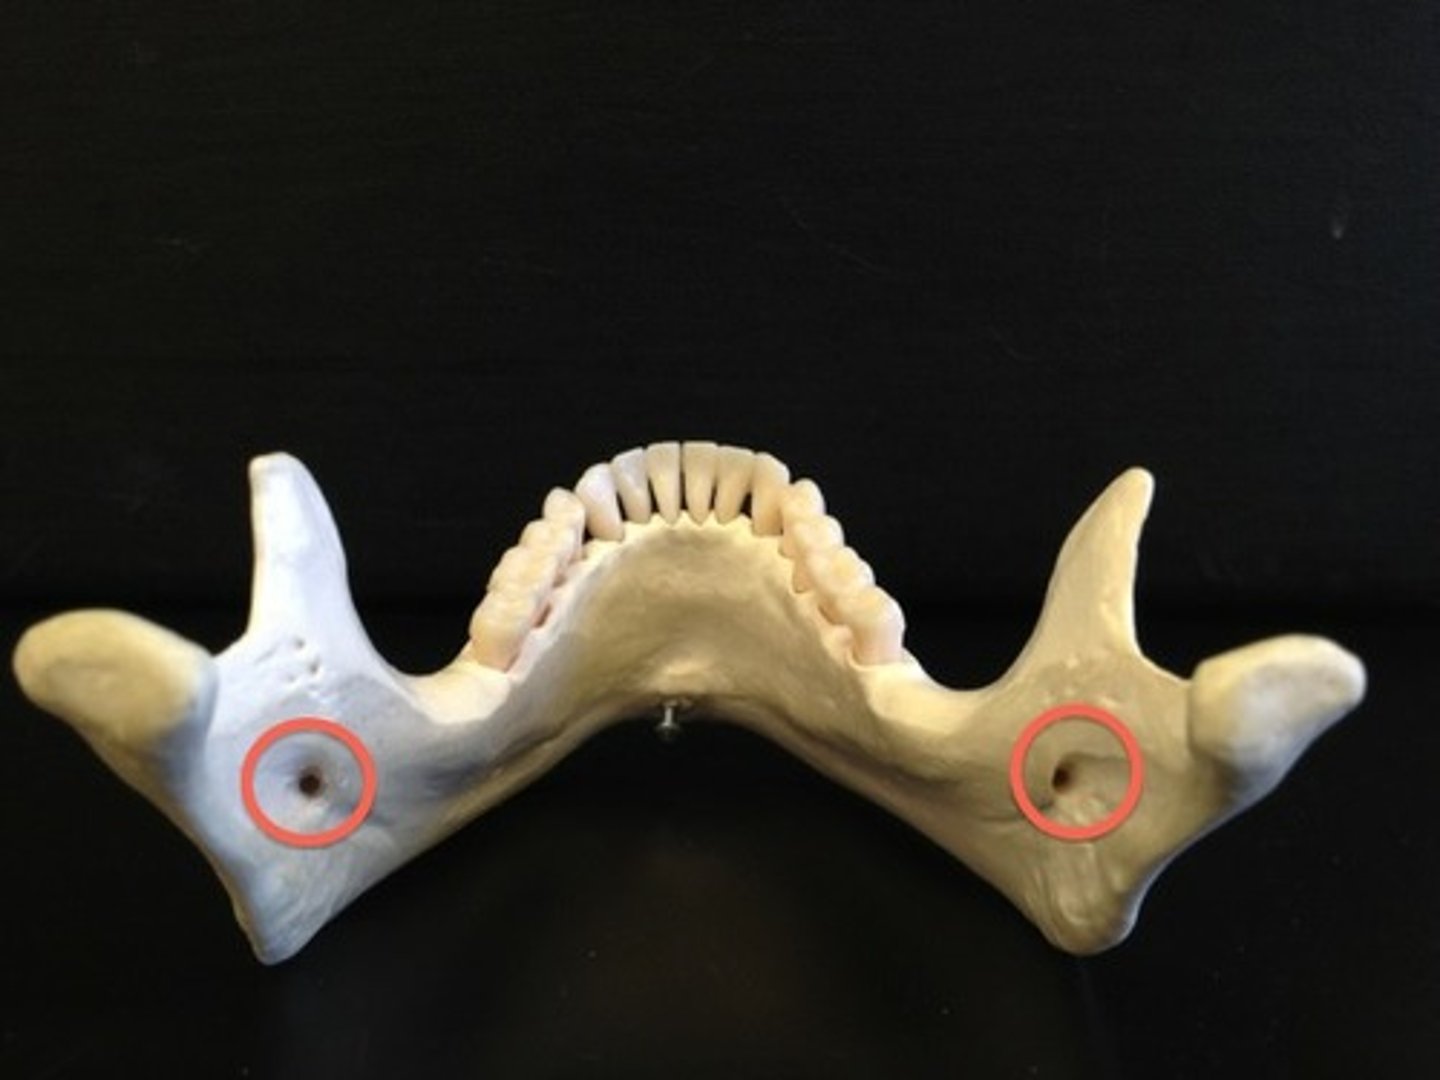

Mental foramen

Name this opening.

Mandibular foramen

Name this bony landmark.

Mandibular foramen

Allows passage of the third branch of the trigeminal nerve (V) on mandible, conveys sensation from the teeth and gums of the mandible

Third division nerve block

Mandibular teeth and gums can be desensitized by an injection of anesthetic near the mandibular foramen